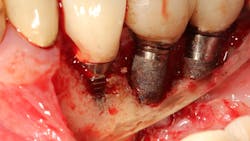

In a recent article discussing two case reports, Nd:YAG and 9.3 micron CO2 lasers were used to detoxify the inner lining of soft tissue surrounding ailing dental implants prior to tissue grafting (figures 1 and 2).12 Lasers can ablate the soft tissue of this particulate (metal) material while killing some of the residual translocated/invasive bacteria, thereby facilitating soft- and hard-tissue healing.

This video demonstrates laser detoxification of the inner lining of the soft-tissue flap, approximating failed dental implant and showing titanium particles embedded into the soft tissue with sparks flying during ablation: